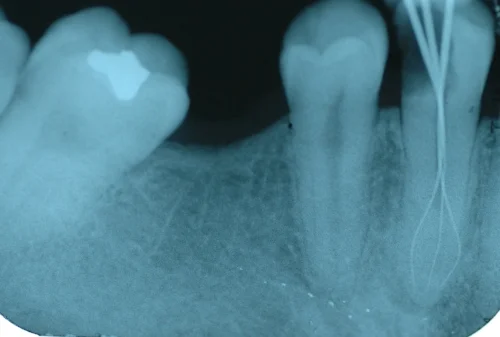

ROOTCANAL.png

Front Teeth Root Canal Treatment

Teeth with history of trauma and deep fillings